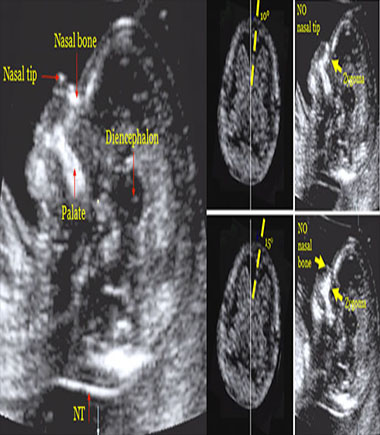

Ecografía Obstétrica

Ecografía 3D y 4D